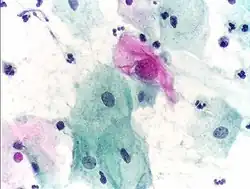

- Micrograph of a normal pap smear

- Micrograph of a Pap test showing a low-grade intraepithelial lesion (LSIL) and benign endocervical mucosa. Pap stain.